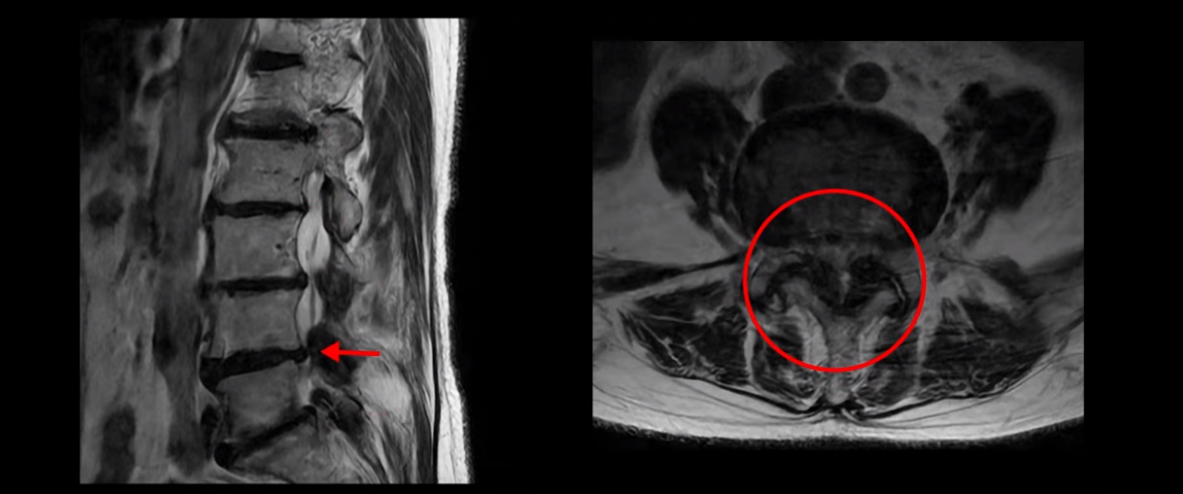

특히 4번 5번에는 심한 중심성 협착이 있고,

5번 1번에는 황색인대가 골화되어 왼쪽 신경 나가는 길이 좁아져 있습니다.

그래서 왼쪽 엉덩이와 다리 통증이 더 심합니다. 이렇게 신경 구멍들이 좁아져 있고 신경이 눌리니까 엉덩이와 다리가 너무 저리고 아프고 힘도 빠져서 몇 걸음도 걷기 어려우니까 지팡이를 짚고 저녁에도 아파서 잠을 못 자는 겁니다.